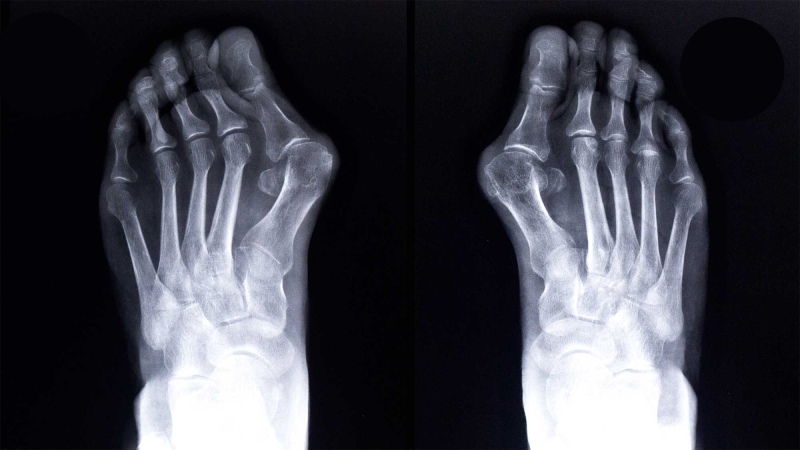

تشخیص زودهنگام هالوکس والگوس نقش مهمی در جلوگیری از پیشرفت آن دارد. تغییر شکل ظاهری انگشت شست، درد در مفصل و التهاب در ناحیه کناری پا از نشانههای بارز این بیماری هستند.

- تصویربرداری: اشعه ایکس برای تعیین شدت انحراف و درجهبندی آن.